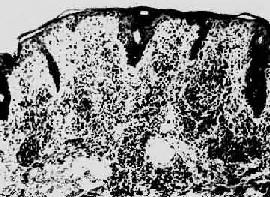

图18-26 梅毒疹 真皮呈致密的淋巴细胞及浆细胞浸润(采自Muir) 第三期梅毒第三期梅毒和第一、二期梅毒之不同在于其破坏性病变,即干酪样坏死和瘢痕形成。病变最常发生于心血管(80%~85%),次为中枢神经(5%~10%),此外肝、骨骼等器官也常发生,实际上几乎任何器官皆可受累。 1.心血管梅毒病变主要发生于动脉(梅毒性主动脉炎)。早在第一期梅毒时,螺旋体已经血道或淋巴道栖止于主动脉壁,潜伏达15~20年之久,才发生病理性损害,是以患者通常皆为40~55岁之中年人。梅毒性主动脉炎的特征为病变起始于主动脉升部,遍及主动脉弓及胸主动脉,每于横膈段截然而止。初始病变为主动脉外膜滋养血管的闭塞性内膜炎,由于管腔的逐渐闭塞,导致主动脉中层弹性纤维和平滑肌的缺血和退行性变,继而由瘢痕取代。镜下,主动脉外膜血管周围有围管性淋巴细胞和浆细胞浸润,小血管内膜增生,中层有灶性微小瘢痕和淋巴细胞、浆细胞浸润(图18-27)。微小的树胶肿偶见。弹性纤维染色可见主动脉中层弹力组织变薄,并有散在的小瘢痕取代了原有的弹力纤维(图18-28)。肉眼观,由于瘢痕收缩及内膜的纤维增生,使内膜表面呈弥漫分布的微细而深陷的树皮样皱纹。又因弹力纤维的广泛破坏,主动脉可呈梭形或囊状扩张,称为主动脉瘤(aortic aneurysm)。患者可因主动脉瘤破裂而猝死。主动脉梅毒的又一病变为主动脉瓣的瓣膜环部病变所致的后果:①环部弹力纤维破坏引起瓣膜环部扩张,②瓣膜呈纤维增生,③瓣叶联合处由于主动脉壁内膜纤维增生和瓣膜收缩而发生瓣叶间的分离。三项因素综合导致主动脉瓣关闭不全。梅毒性主动脉瓣病变的特点是瓣叶之间绝无粘连,故关闭不全而不伴有狭窄,这是和风湿性主动脉瓣病变不同之处。主动脉瓣关闭不全,使左心室异常肥大和扩大,以致心重可达千克左右,乃有“牛心”(car bovinum)之称。患者最终死于心力衰竭。此外,主动脉根部瘢痕又造成冠状动脉口狭窄,导致心绞痛发生。第三期梅毒的心血管病变主要涉及主动脉,仅偶有心肌发生树胶肿者。